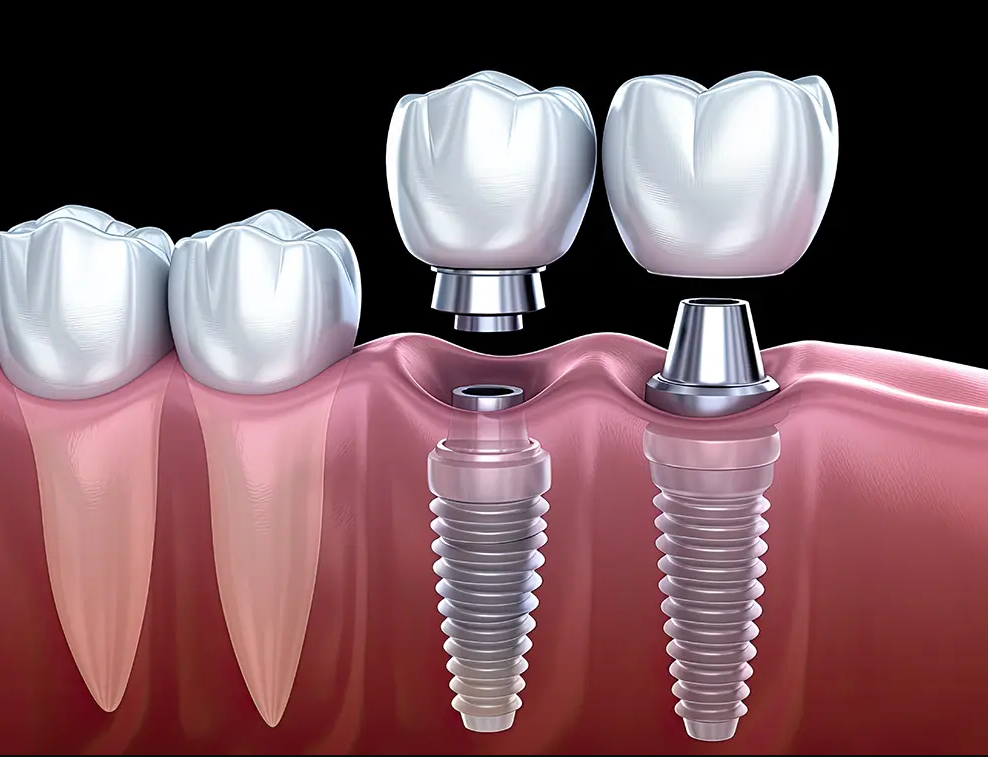

Diş İmplantı Tedavisi